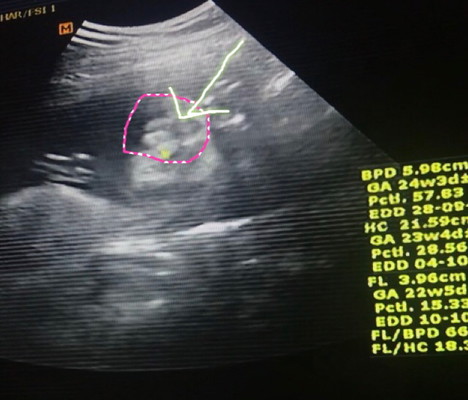

ขอเสียงทีมลูกสาวเดือนกันยาหน่อยจ้า เอารูปซาวมาอวดกันหน่อยเร๊วว ? บ้านนี้หมอบอกลูกสาว100% เห็นมาเป็นกลีบแบบนี้เลย สมใจอิแม่นัก????

สาวน้อยกันยา ชัดแจ๋วเลยค่ะ ☺️💕